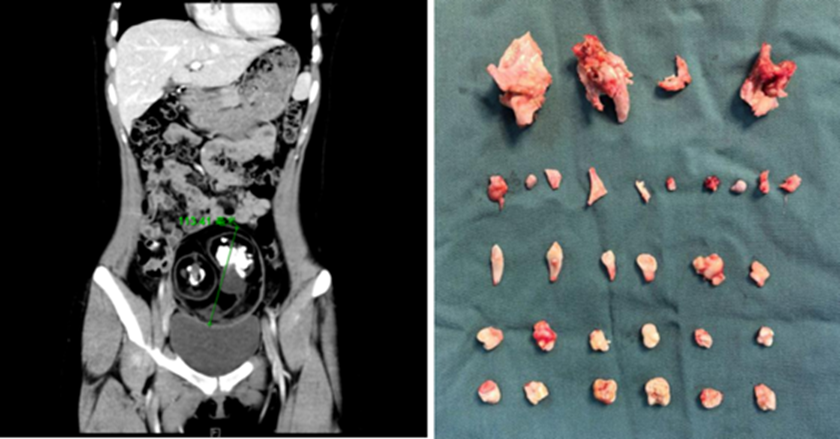

Bệnh nhân cho biết cơn đau xuất hiện đột ngột ở vùng bụng dưới bên phải khi đang tập thể dục tại nhà. Cơn đau kéo dài, không thuyên giảm khiến cô phải nhanh chóng đến bệnh viện để kiểm tra. Kết quả siêu âm khiến cả bệnh nhân lẫn bác sĩ bất ngờ khi trong bụng cô có một khối u đường kính khoảng 12cm, thậm chí trên hình ảnh còn thấy thấp thoáng cấu trúc giống răng và xương.

Bác sĩ nhận định đây nhiều khả năng là u quái buồng trứng, tên khoa học là “teratoma buồng trứng”. Đây là loại u hình thành từ tế bào sinh dục, có thể chứa nhiều loại mô khác nhau như tóc, răng, xương, thậm chí cả mô mỡ. Dù phần lớn u quái là lành tính, nhưng khi khối u phát triển lớn hoặc có nguy cơ xoắn, vỡ, người bệnh có thể gặp biến chứng nguy hiểm và cần phẫu thuật sớm.

Thông qua một đường rạch nhỏ khoảng 2cm tại rốn - vị trí có nếp gấp tự nhiên - các bác sĩ đã bóc tách và lấy trọn khối u kích thước 12cm ra ngoài. Khi kiểm tra bên trong khối u, chính đội ngũ y tế cũng không khỏi bất ngờ khi phát hiện tới 24 chiếc răng với hình dạng khác nhau, cùng với mô xương có đường kính gần 5cm.